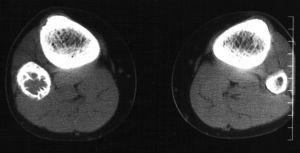

Se realizó a continuación un estudio mediante tomografía computarizada (TC) (fig. 2), obteniendo cortes axiales sin contraste y posteriores reconstrucciones multiplanares. Los hallazgos eran similares a la radiografía simple, mostrando una lesión lítica, mínimamente expansiva y con septos gruesos, sin provocar destrucción de la cortical ni masa de partes blandas, y provocando un leve festoneado endostal. En este caso no se realizó resonancia magnética (RM) y se practicó una biopsia percutánea con el resultado histológico de fibroma desmoplásico. A continuación se le realizó una biopsia quirúrgica y fue tratada mediante curetaje y relleno de la cavidad con cemento tipo Norian.

Fig. 2.--Tomografía computarizada (imagen axial y reconstrucción coronal). Se identifica un reborde grueso esclerótico y finos septos internos sin lisis de la cortical o reacción perióstica.